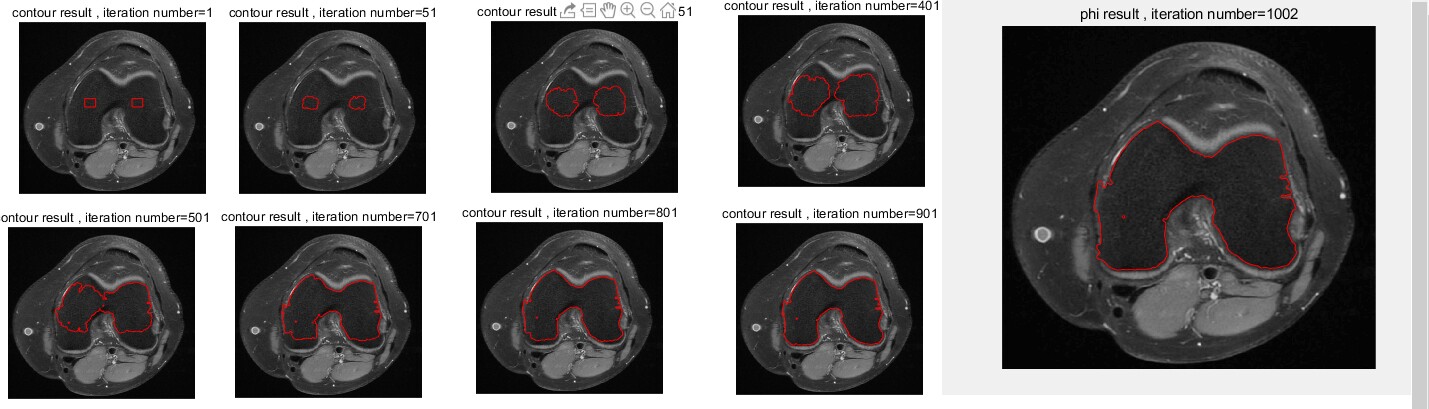

基于水平集进化的轮廓提取

水平集进化(LSE)是一种著名的轮廓提取(确定对象边界)和对象分割的方法。

LSE的主要缺点是重新初始化步骤。

为了消除提取出的物体边界(轮廓)的不规则性,必须执行该步骤。

基本上,水平集必须根据一些基于距离的准则定期重新初始化。